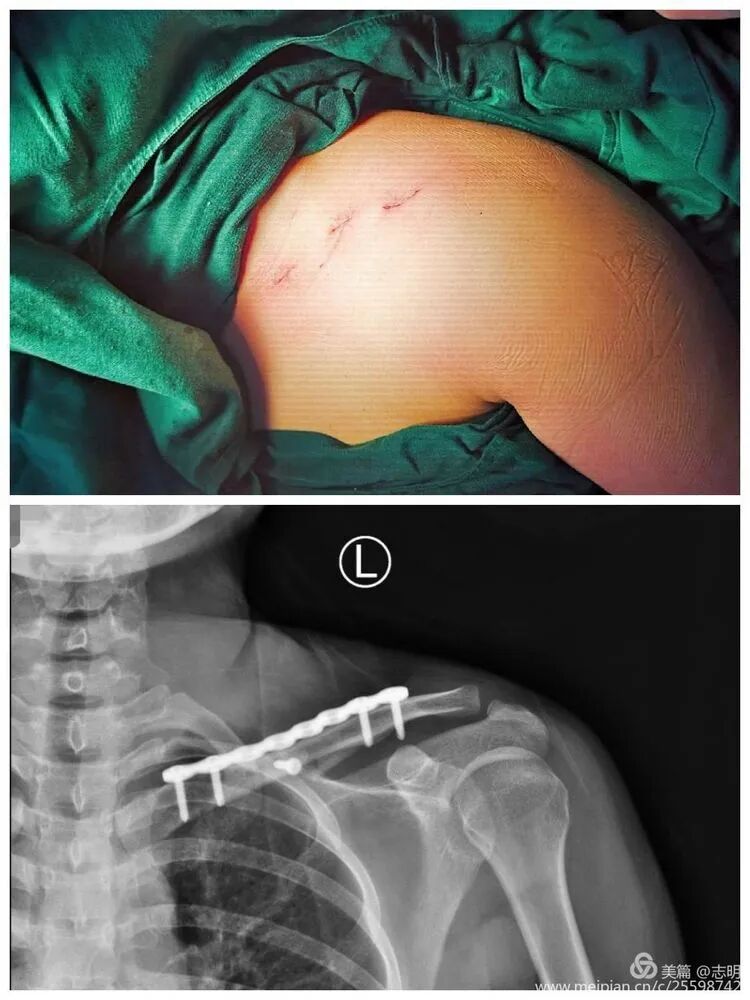

(Clinical image of small, well-healed MIPO incisions). -

(Another clinical view of minimal scarring). -

(Post-fixation X-ray showing the plate and screws in place). -

(Another post-fixation X-ray).

(Post-fixation X-ray). -

(Healed fracture X-ray). -